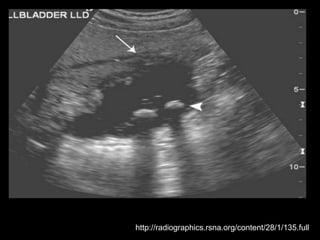

http://radiographics.rsna.org/content/28/1/135.full

Duplicação da Vesícula Biliar

Ocorre em 0,025% da população;

Causada pela revacuolização incompleta da

vesícula biliar primitiva, que resulta na

persistência de um septo longitudinal.

A cavidade de cada vesícula precisa ter seu próprio

ducto cístico.

A maioria dos casos de duplicação relatados inclui

um quadro de colecistite com cálculos.

Várias condições podem simular vesícula

duplicada.

Exemplos: VB dobrada, VB bilobada, cisto de

colédoco, líquido perivesicular, divertículo da VB,

VB atravessada por feixe vascular e

adenomiomatose focal;

Complicações: torção, papiloma, carcinoma,

obstrução do ducto comum e cirrose biliar;

Foram relatadas vesículas triplas e quádruplas!!!